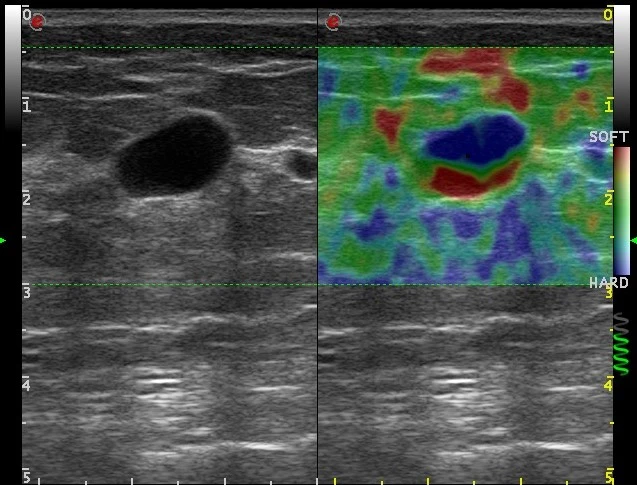

MyLab™9 Platform - Dual ElaXto characterization on breast lesion

MyLab™9 Platform - Dual ElaXto characterization on breast lesion